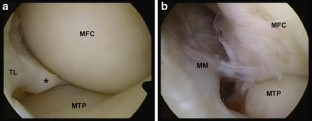

Fig. 1